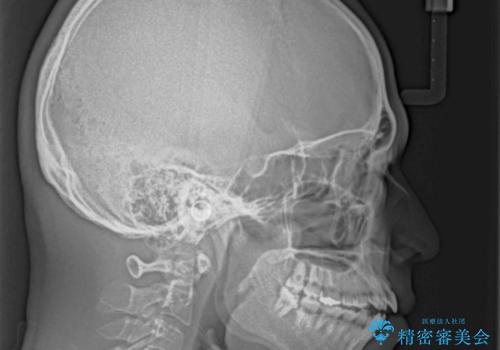

- 前歯の開咬と叢生を気にして来院された患者様です。

開咬の治療は、前歯を閉じるように動かすとともに、上下臼歯を圧下(骨内にめり込ませる)させることで進めて行きます。

インビザラインは臼歯の圧下を効果的に行えるため、インビザラインを用いて矯正治療を行うこととしました。また、アンカースクリューを用いて、口元の突出感の改善を図りました。